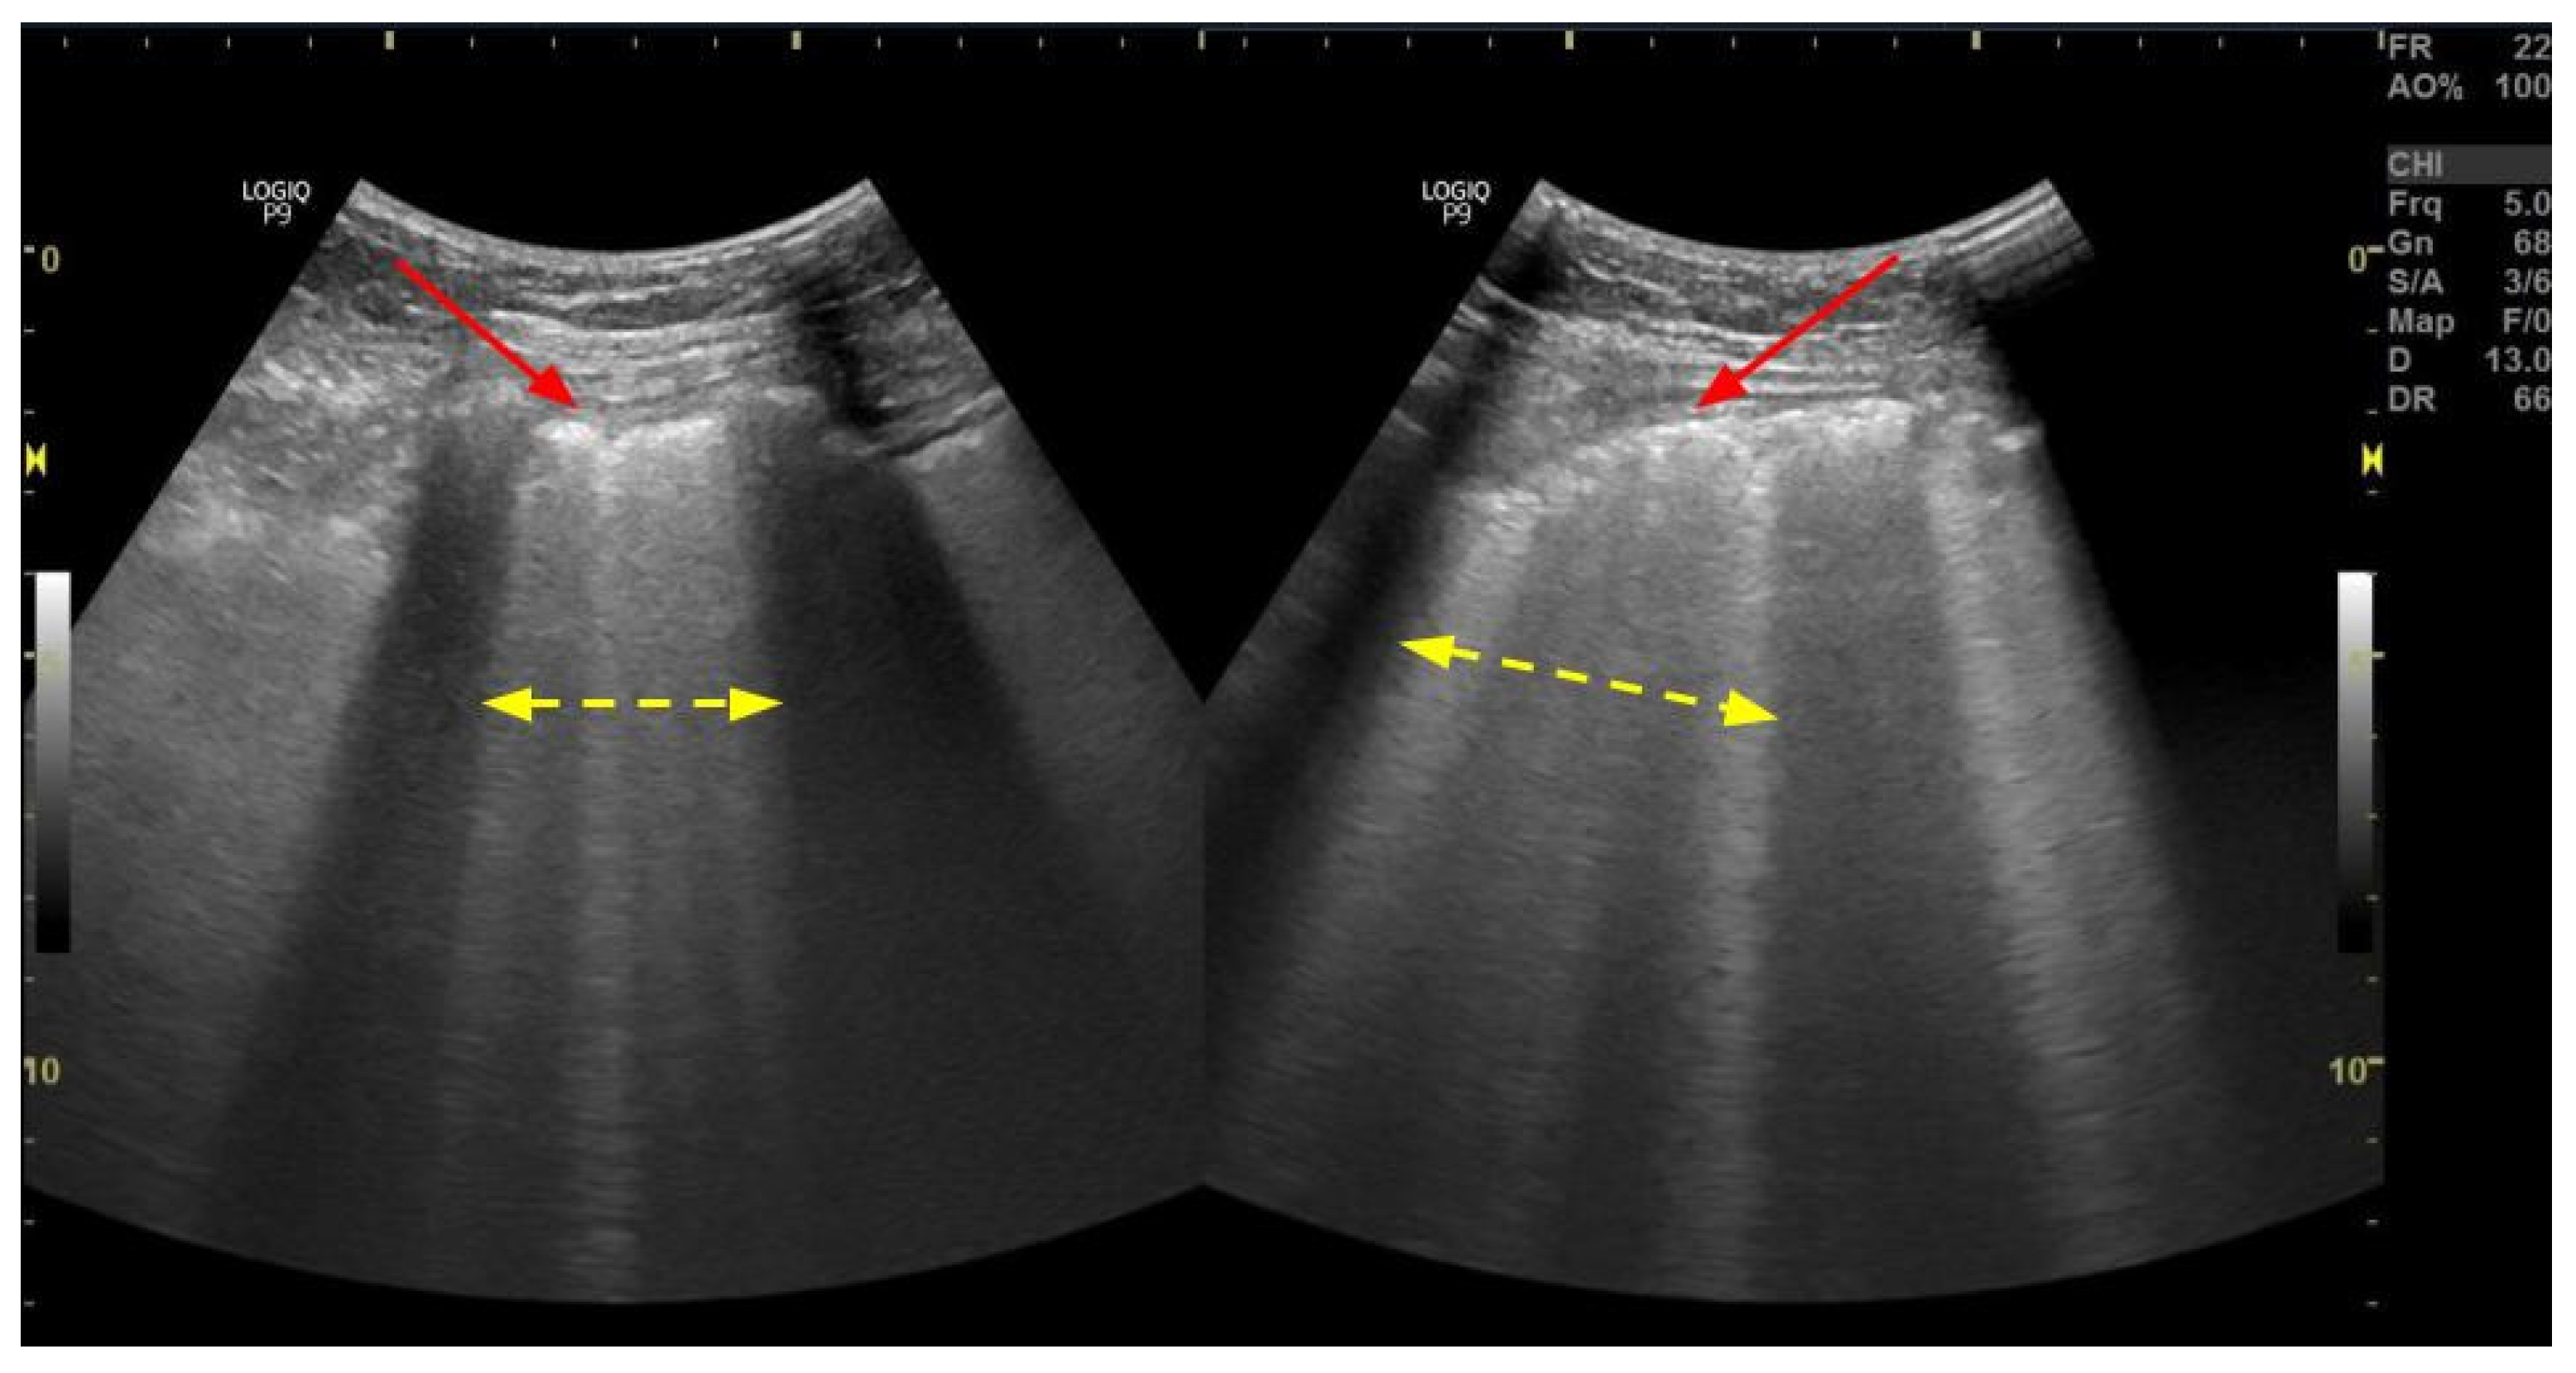

3.1. B-Lines

- Volpicelli, G.; Elbarbary, M.; Blaivas, M.; Lichtenstein, D.A.; Mathis, G.; Kirkpatrick, A.W.; Melniker, L.; Gargani, L.; Noble, V.E.; Via, G.; et al. International Evidence-Based Recommendations for Point-of-Care Lung Ultrasound. Intensive Care Med. 2012, 38, 577–591. [Google Scholar] [CrossRef]

- Picano, E.; Scali, M.C.; Ciampi, Q.; Lichtenstein, D. Lung Ultrasound for the Cardiologist. JACC Cardiovasc. Imaging 2018, 11, 1692–1705. [Google Scholar] [CrossRef]